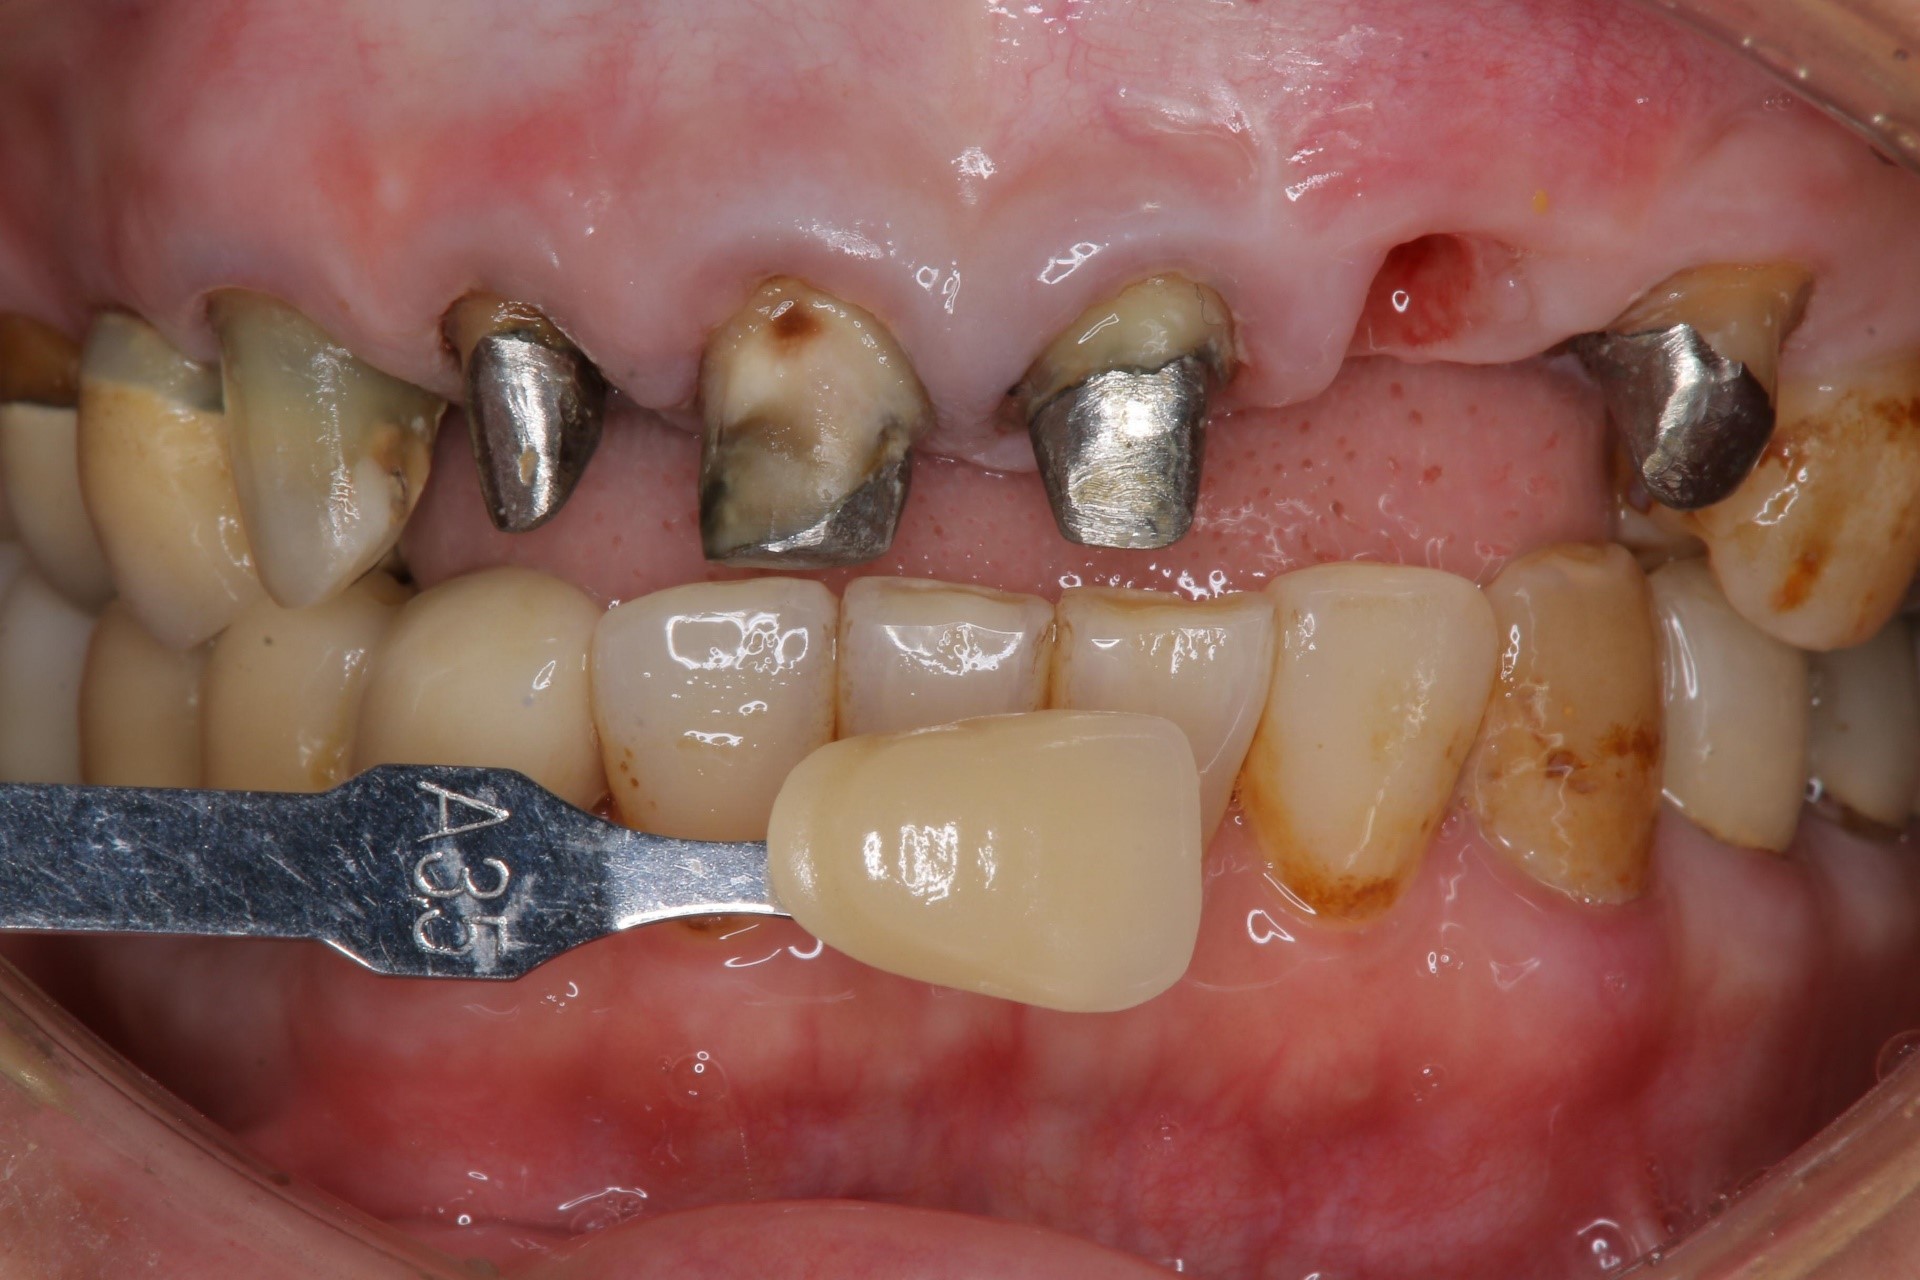

照相比色

術前、術後比較